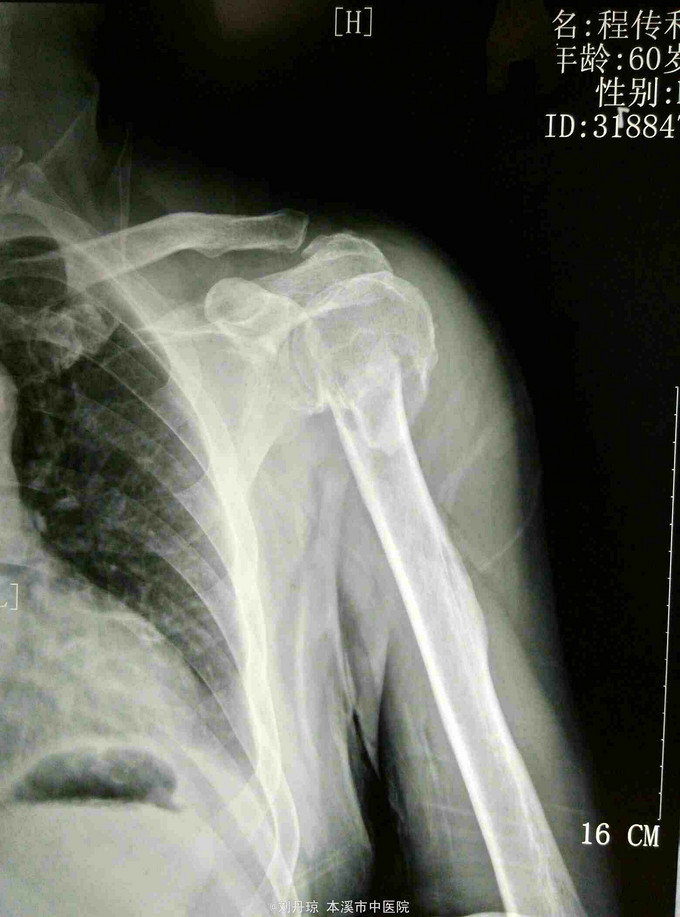

患者男60岁。主诉:左肩刺痛,活动受限2小时。 病史:患者2小时前散步时不慎摔倒,左肩刺痛, 活动受限。伤后由朋友送入我院。

左肩部畸形、肿胀明显,外科颈部压痛阳性,左肩部功能障碍。DR: 左肱骨近端粉碎骨折,分解为四部分,移位明显。

诊断:左肱骨近端粉碎骨折 治疗:手法整复,夹板固定。接骨丹口服。

随访1年。此四部分骨折,肱骨近端四个解剖部分完全分离,肱骨头移向后方,肱骨头血运破坏严重,容易发生缺血坏死。